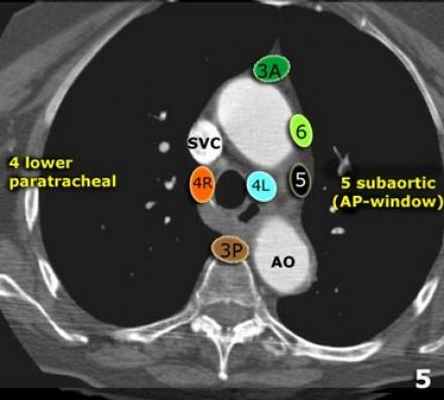

В этой статье представлены иллюстрации и КТ-изображения для лучшего понимания этой классификации.

4L Нижние паратрахеальные от верхнего края дуги аорты до верхнего края левой главной легочной артерии

5. Субаортальные лимфатические узлы располагаются в аортопульмонарном окне, латеральнее артериальной связки, они расположены не между аортой и легочным стволом, а латеральнее них.

Узлы 5 группы (аортопульмонального окна) расположены кнаружи от артериальной связки.

На левом изображении над уровнем легочного ствола представлены нижние паратрахеальные узлы слева и справа, так же здесь представлены узлы 3 и 5 групп.

Изображение слева выше уровня карины. Слева от трахеи 4L узлы. Обратите внимание что они расположены между легочным стволом и аортой, но не в аортопульмональном окне, потому что они лежат медиальнее артериальной связки. Лимфатические узлы латеральнее легочного ствола относятся к 5 группе.

5. Субаортальные лимфатические узлы

Субаортальное или аортопульмональное окно расположено кнаружи от артериальной связки и проксимальнее первой ветви левой легочной артерии и лежит в пределах медиастинальной плевры.

Группы лимфатических узлов на аксиальных компьютерных томограммах

4. Нижние паратрахеальные: ниже верхнего края дуги аорты до уровня главного бронха

5. Субаортальные (аортопульмональное окно): лимфатические узлы кнаружи от артериальной связки или кнаружи от аорты или левой легочной артерии.